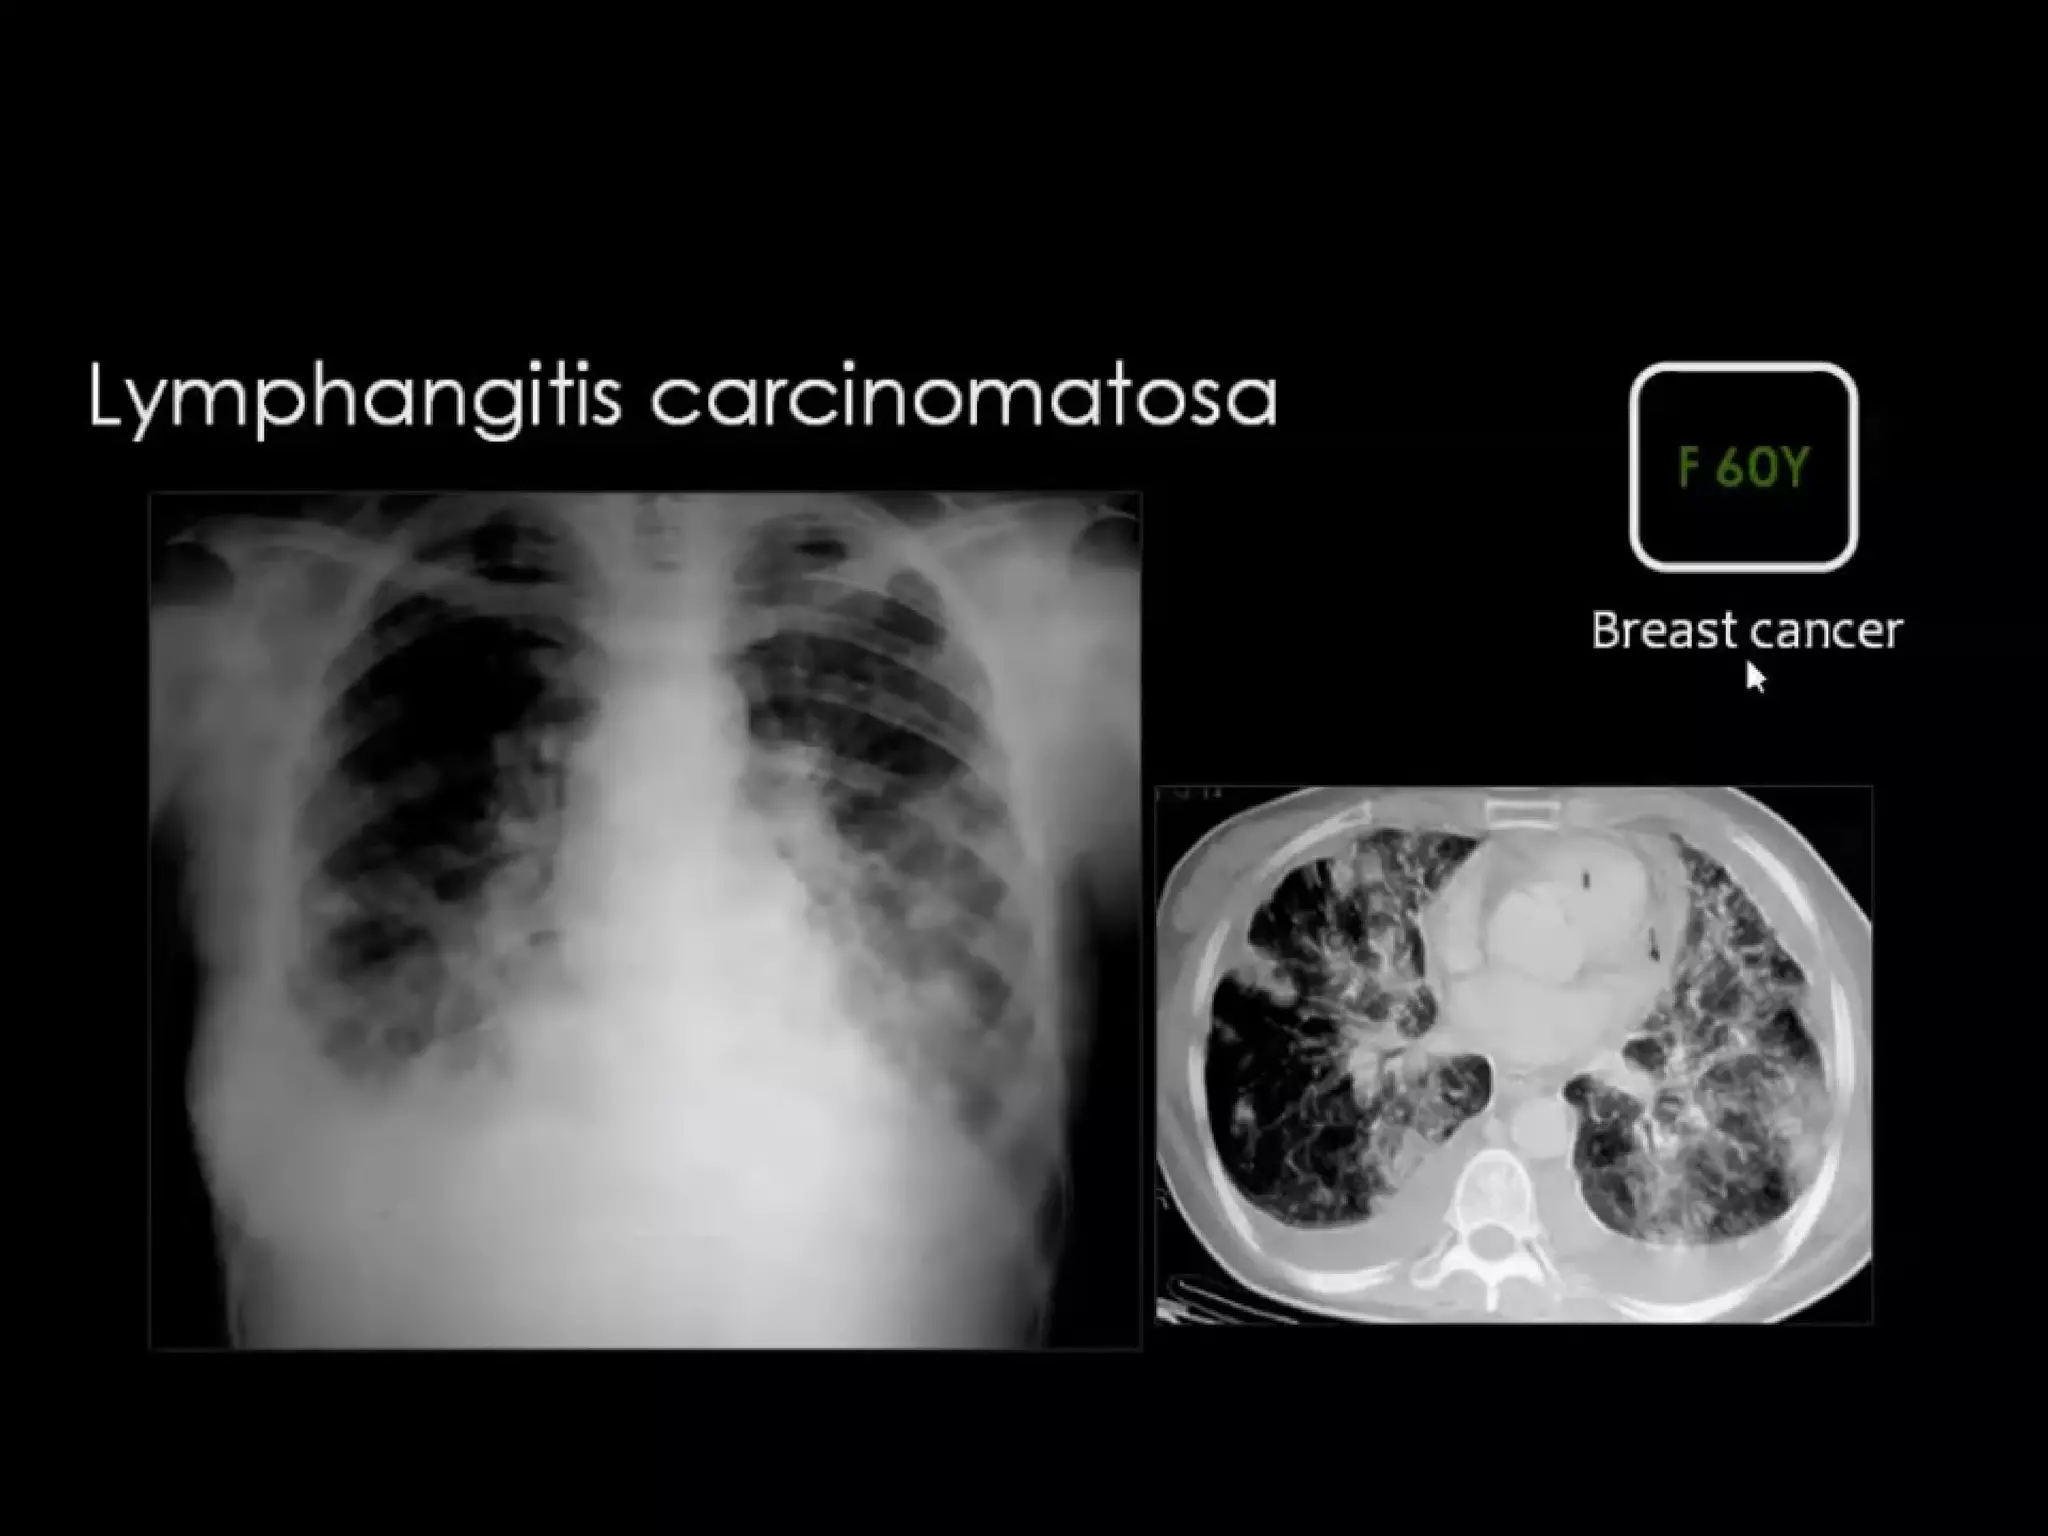

Focal irregular septal thickening in lymphangitic

carcinomatosis

Lymphangitic Carcinomatosis

results from hematogenous

spread to the lung, with

subsequent invasion of

interstitium and lymphatics.

The presenting symptoms are

dyspnea and cough and can

predate the radiographic

abnormalities.

In many cases however the

patients are asymptomatic.

is seen in carcinoma of the

lung, breast, stomach, pancreas,

prostate, cervix, thyroid and

metastatic adenocarcinoma

from an unknown primary.

Focal irregular septalthickening in lymphangitic carcinomatosis Lymphangitic Carcinomatosis results from hematogenous spread to the lung, with subsequent invasion of interstitium and lymphatics. The presenting symptoms are dyspnea and cough and can predate the radiographic abnormalities. In many cases however the patients are asymptomatic. Lymphangitic Carcinomatosis is seen in carcinoma of the lung, breast, stomach, pancreas, prostate, cervix, thyroid and metastatic adenocarcinoma from an unknown primary.